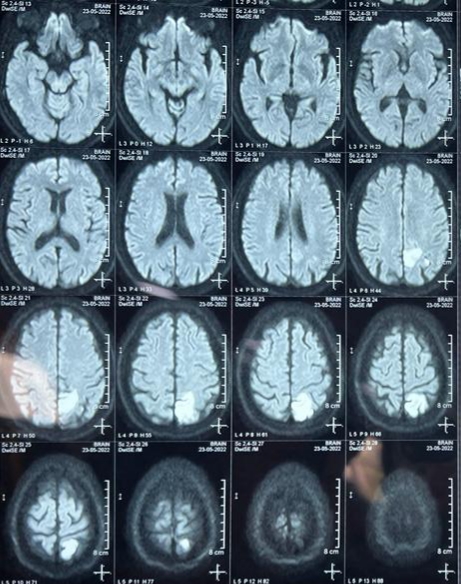

WEEK 3 : PARASAGITTAL INFARCT WITH LOWER LIMB MONOPARESIS

WEEK 4 :FORNIX INFARCT WITH ACUTE DELIRIUM